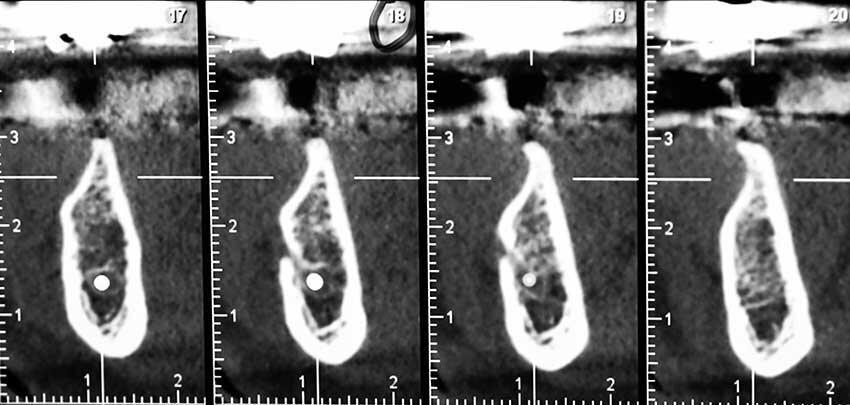

La CBCT dell’arcata inferiore evidenziava una cresta ossea edentula molto riassorbita in senso orizzontale con uno spessore medio non superiore ai 3 mm (Figg. 1b, 1c). Dopo una preventiva seduta di igiene orale veniva programmato un intervento di rigenerazione ossea con ausilio della tecnica della lamina corticale (Fig. 2).

Dopo aver somministrato l’anestesia locale con Articaina con adrenalina 1.200.00 veniva eseguita un’incisone con lama 12 sulla cresta edentula facendo attenzione a dividere l’esigua quantità di gengiva cheratinizzata in maniera equa tra i due lembi, vestibolare e linguale. La cresta esposta confermava quanto osservato sulla CBCT, lo spessore in cresta era di 3 mm nella zona distale al canino e andava ad assottigliarsi fino ad 1 mm nella zona dei molari. In prossimità del sito 46 si trovava un residuo radicolare, che veniva rimosso e nella stessa posizione veniva inserito un impianto di diametro standard (4 mm) mentre gli impianti nei siti dei premolari e del secondo molare erano di diametro ridotto (3.5) (Fig. 4).

La rx post-operatoria evidenzia bene come nel sito 46 l’impianto fosse ancorato all’osso solamente dalla sua porzione apicale, mentre l’immagine clinica (Fig. 5) mostra quanto ognuno dei quattro impianti (Neodent-Straumann) presentasse una evidente deiescenza vestibolare con almeno 5-6 spire esposte fuori cresta e una evidente insufficienza di volume in senso orizzontale (Fig. 6). Per questa specifica situazione clinica si selezionò un materiale (GTO Osteobiol) da innesto con caratteristiche particolari, appiccicoso e capace di creare e mantenere il volume anche in una situazione anatomicamente sfavorevole. Questo bio-materiale è composto da osso suino collagenato associato a un gel termo sensibile (TSV gel) che gli consente di “gellificare” e diventare solido al contatto con l’umidità della bocca. Queste caratteristiche lo rendono facilmente plasmabile al difetto e nello stesso tempo stabile, dalla figura 6 si può notare come questa stabilità consenta di apporre una quantità di materiale adeguato a correggere il difetto della cresta e a proteggere le spire degli impianti altresì esposte (Fig. 7).